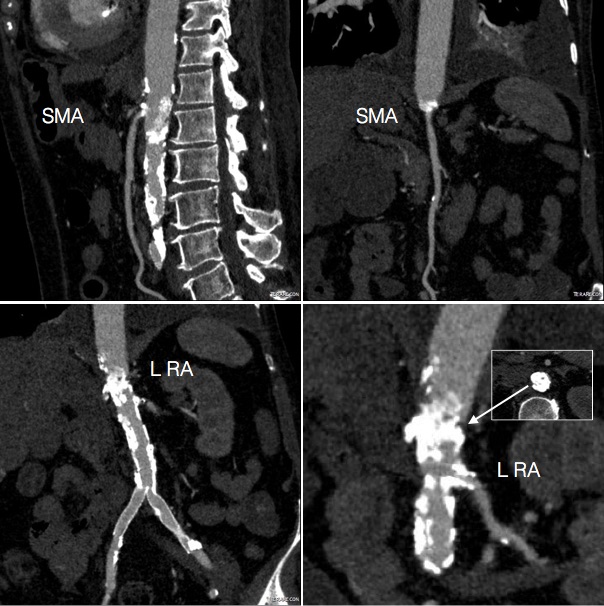

The patient is a woman in her 60’s who self referred for complaint of abdominal pain, weight loss, and rest pain of the lower extremities. She is a 40 pack year smoker and had severe COPD, hypertension, congestive heart failure with mitral regurgitation, chronic kidney disease stage IV, and ischemic rest pain of the legs. She had a 30 pound weight loss due to severe postprandial abdominal pain. She had bloody stools. Her kidney function was worsening, and dialysis was being planned for likely renal failure but she was against dialysis. She had consulted several regional centers but was felt to be too high risk for surgery and with her refusal of dialysis, would be a high risk for renal failure and death with intervention. Physical examination revealed weakened upper extremity pulses, and nonpalpable lower extremity pulses and a tender abdomen. In clinic, she developed hypoxia and dyspnea and was admitted directly to the ICU.

CTA (above) revealed severely calcified atherosclerotic plaque of her visceral segment aorta occluding flow to her mesenteric and renal arteries and to her leg. The right kidney was atrophic. The left kidney had a prior stent which looked crushed. The infrarenal aorta was severely diseased but patent and there were patent aortic and bilateral iliac stents.

Access for intervention was via the left brachial artery. Aortography showed the severe stenosis at the origin of the SMA and the nearly occlusive plaque in the visceral segment aorta.

The plaque was typical of the coral reef type, and had an eccentric channel that allowed passage of a Glidewire. Access into the left renal artery was achieved. Its stent was patent but proximally and distally there were stenoses; this was treated with a balloon expandable stent. The path to it was opened with a balloon expandable stent to 8 mm from femoral access. This was the improvement the renal needed. A large nitinol stent was placed from this access in the infrarenal aorta when severe disease above the iliac stents was encountered. The SMA was then accessed and treated with a bare metal stent.

Her creatinine improved, as did her intestinal angina. She was discharged home. She later returned a month after the procedure with complaints of nausea and vomiting and right lower quadrant abdominal pain and was discovered to have an ischemic stricture of her small bowel. This was removed laparoscopically and she recovered well. She recovered her lost weight and now a year and a half later, remains patent and symptom free.